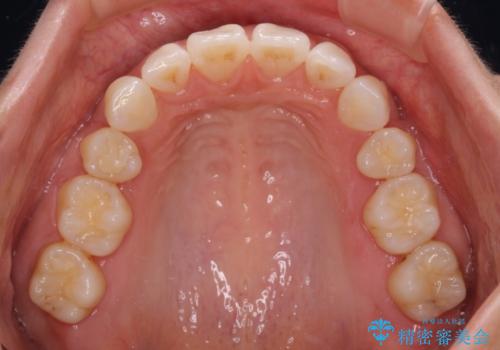

尖った前歯を引っ込めたい 目立たないワイヤー装置での抜歯矯正

- 飛び出した前歯を気にして来院された患者様です。

口元を引っ込めるために上下左右の第一小臼歯4本を抜歯することとしました。

途中妊娠と出産がありましたが、予定よりも早く治療を終えることができました。